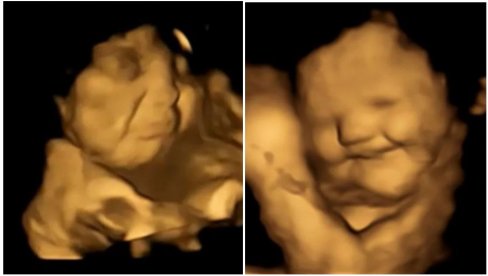

U studiji objavljenoj u časopisu Psychological Science, naučni tim je naveo da su arome od majčine ishrane prisutne u plodovoj vodi. Centri za ukus mogu da otkriju hemikalije koje daju ukus već posle 14 nedelja od začeća, dok molekule mirisa fetusi mogu da osete posle 24 nedelje.

Plačni izrazi lica bili su dva puta češći kada su majke konzumirale kapsule sa keljom u poređenju sa fetusima čije su majke uzimale kapsule sa šargarepom ili nisu uopšte uzimale kapsule. U slučaju kapsula sa ukusom šargarepe, lica nerođenih beba su često dobijala izraz osmehivanja.

Foto: FETAP Study/Fetal and Neonatal Research Lab/Durham University